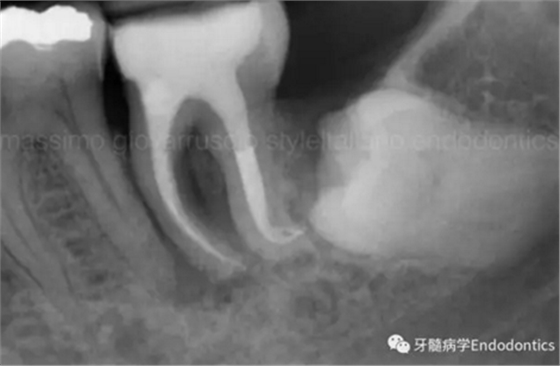

圖3.存在細(xì)小狹長(zhǎng)、可能多維的復(fù)雜根管解剖時(shí),使用10號(hào)K銼不可能立即疏通根管到達(dá)根尖止點(diǎn)。隨后醫(yī)生應(yīng)嘗試使用更小的銼探查以達(dá)到根尖。但是,通常不需要使用6號(hào)和8號(hào)K銼對(duì)到達(dá)根尖的引導(dǎo)通道進(jìn)行擴(kuò)大,除非是特別困難的病例。

圖4.根尖孔通常比10號(hào)K銼大,因此感到任何阻力時(shí)可能是因?yàn)楦艿膹澢虿灰?guī)則。因此,有效的建立可重復(fù)的引導(dǎo)通道的方法應(yīng)是使用10號(hào)K銼逐步擴(kuò)大開放根管,此時(shí)也將產(chǎn)生臺(tái)階或根管堵塞的可能性降到最低。